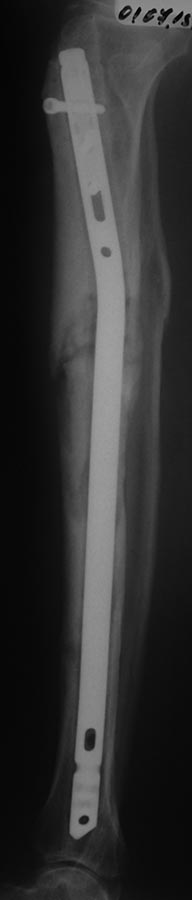

Добрый вечер. Прошу ваше мнения по данному случаю. Поступила Пациентка 50 лет, жительница села. В 18.12.2012 г. в пьяном угаре оступилась о порог двери, после чего поступает в отделение с переломом голени (первоначальных снимков нет). 19.12.2012 г. был выполнен закрытый БИОС, благополучно выписана с рекомендациями. На назначенное время не явилось. Пришла в 26.02.2013 г., тогда удалили 2 блокирующих винта, и в 20.05.2013 г. тоже убрали 2 блокирующих винта. Также благополучно потерялась, появилась в октябре 2014 г., с признаками несращения правой большеберцовой кости. После чего был выполнен реостесинтез штифтом. На данный момент беспокоит боли в области коленного, голеностопного суставов и средней трети голени, отек голени. Как быть дальше????Извиняюсь, 1й БИОС произведен открыто. прилагается фото ноги.

Надо исключить/подтвердить инфекцию (CРБ, лейк, СОЭ). Рентгенологически похоже на остеомиелит

Добрый день! ИМХО: остеотомия м/б кости и осевая нагрузка, при инфекции дополнительно - развертками по каналу, санация канала антисептиками, штифт с цементным а/б покрытием.

Ротационная нестабильность дистального отломка....